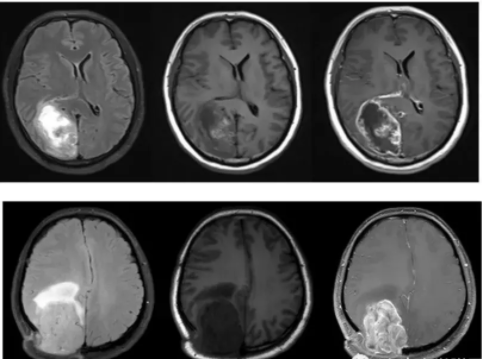

膠質(zhì)瘤復(fù)發(fā)診斷:是惡性進(jìn)展還是放射性壞死?

然而,在某些情況下,可能需要注意細(xì)微的差異:更球形、界限更清晰的形狀可能提示膿腫而不是復(fù)發(fā)性惡性膠質(zhì)瘤;周圍水腫的彌漫性、不規(guī)則邊緣模式可能提示放射性壞死而不是復(fù)...